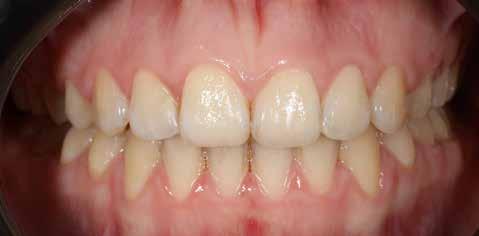

Ebben a cikkben egy 16 éves lánypáciens esetét szeretném bemutatni (1–7. képek)

A fix fogszabályozó készülék mindössze 16 hónapos kezelés után került eltávolításra! Páciensünk legnagyobb örömére állcsontműtét nélkül sikerült mind az arcesztétikai, mind a funkcionális rehabilitáció (13–18. képek)